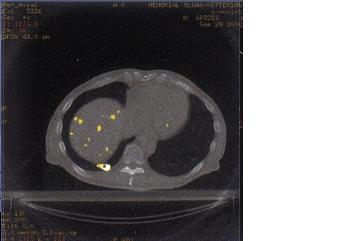

Funkční zobrazení – předpověď efektu

léčby

Stanovení velikosti hypoxie

- PET, SPECT

markery hypoxie

- MRI

EPI (dynamické zobrazování s kontrastem), BOLD (hemoglobin), MR angiografie: perfuze, permeabilita, objem krve, funkce a reaktivita cév, angiogeneze

Agresivita tumoru, grading

MR spektroskopie ( 1H, 31P )

EPI ( dynamické zobrazování s použitím GdDTPA )

Viabilita tumoru při a po léčbě

PET ( FDG )

MR angiografie